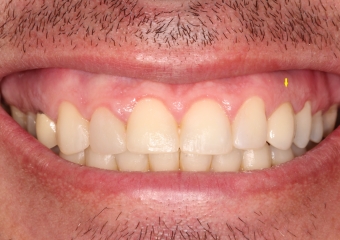

Janeiro de 2016, Controle de 3 anos